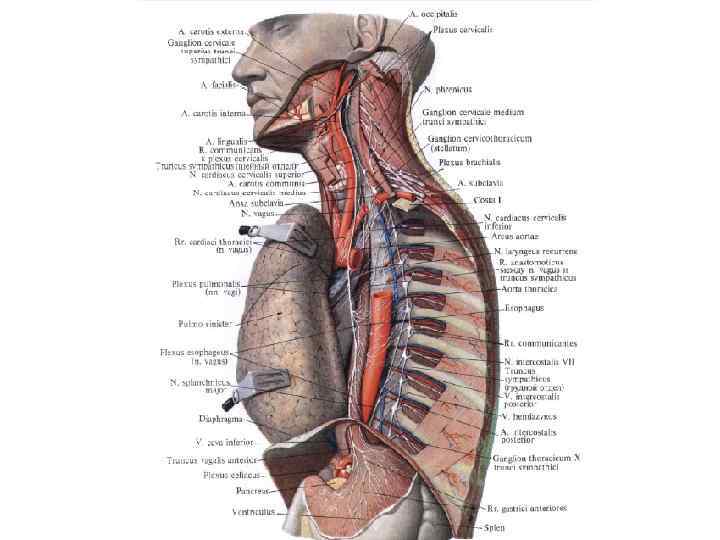

Пищевод (oesophagus) – полый трубчатый орган. Длина у взрослого человека – 25 -27 см. Pars cervicalis. 5 -7 см. Pars thoracica. 16 -18 см. Pars abdominalis. 1, 5 -4 см.

Пищевод (oesophagus) – полый трубчатый орган. Длина у взрослого человека – 25 -27 см. Pars cervicalis. 5 -7 см. Pars thoracica. 16 -18 см. Pars abdominalis. 1, 5 -4 см.

Скелетотопия пищевода. Начинается на уровне VI шейного позвонка и впадает в желудок на уровне XII грудного позвонка.

Скелетотопия пищевода. Начинается на уровне VI шейного позвонка и впадает в желудок на уровне XII грудного позвонка.